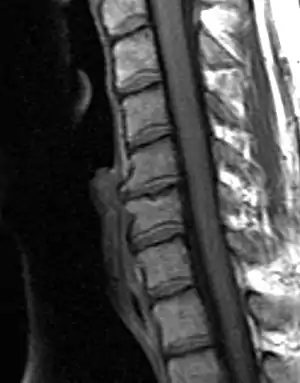

| Degenerated disc between C5 and C6 (vertebra at the top of the picture is C2), with osteophytes anteriorly (to the left) on the lower portion of the C5 and upper portion of the C6 vertebral body. | |

MRI of the lumbar spine, intervertebral disc degeneration